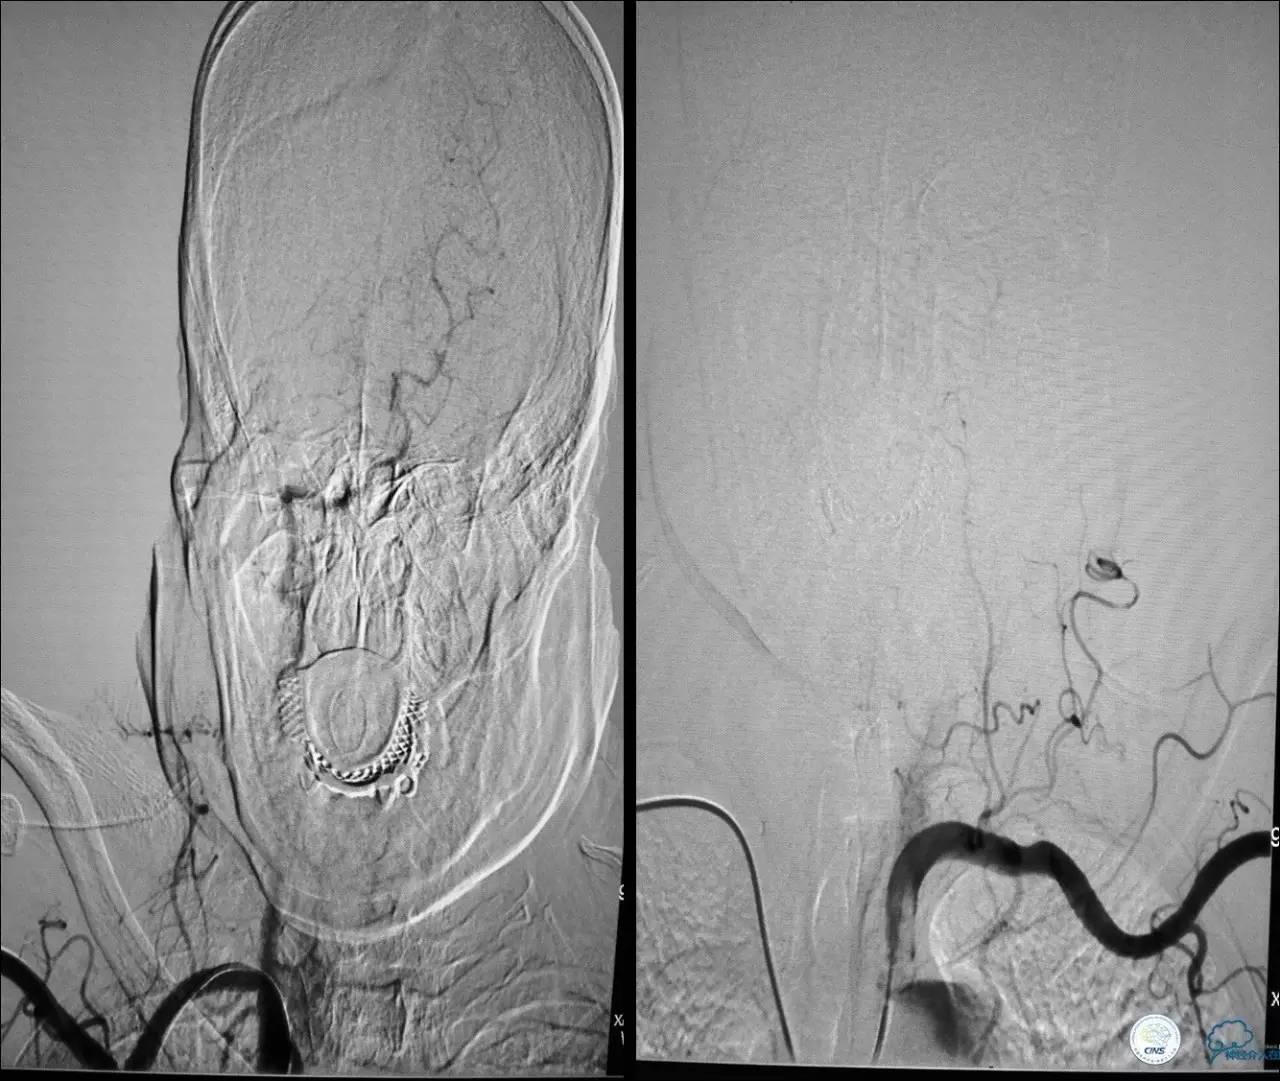

》男,74岁。

》主诉:突发左侧肢体抽搐伴口角歪斜两月余,右侧肢体抽搐三天余。

》查体:左上肢肌力Ⅲ级,左下肢肌力Ⅳ级,右侧肢体肌力Ⅴ级。

》既往史:高血压病史。

》患者术后4小时出现右侧肢体无力,伴有癫痫样症状。

》考虑小栓子脱落,术中曾有后扩。